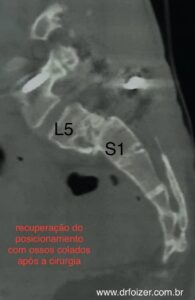

- A artrodese por via posterior (o acesso a coluna é realizado pelas costas- figura y TLIF) sendo colocado um espaçador (calço) para auxiliar na consolidação (“calcificação”) óssea juntamente com parafusos para manter o posicionamento.

A artrodese realizada por via anterior (o acesso a coluna é realizado pelo abdome e pelas costas) sendo colocado um espaçador através de uma incisão pelo abdome. Esta técnica tem a vantagem de proporcionar menor lesão a musculatura extensora lombar que é sabidamente muito importante para manter a “saúde” dos discos intervertebrais. Esta técnica é chamada de ALIF, da sigla em inglês que significa fusão intervertebral lombar anterior. Sua indicação possui características relacionadas a cirurgias prévias no abdome ou não, além de características especificas das relações entre a coluna e a bacia do paciente.

Figura y: tomografia mostrando uma espondilolistese de alto grau entre a quinta vertebra lombar e a primeira vertebra sacral (da bacia) com escorregamento grave. A figura a direita mostra a correção do escorregamento após cirurgia (TLIF). Fonte: acervo Dr. Guilherme Foizer. Publicação autorizada pelo paciente.